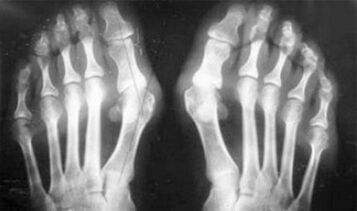

- Stoffwechselverletzung (Gicht).

Der Unterschied zwischen Arthritis und Arthrose der Finger und der Hände der Hände besteht darin, dass die erste Krankheit geheilt und die zweite nicht. Bei Arthritis werden die Synovialgehäuse und die Artikulationskapsel berührt.

Wie Sie sehen können, sind die Unterschiede in den Symptomen unbedeutend: In beiden Fällen gibt es Schmerzen, Starrheit und Müdigkeit. Arthritis und Arthrose können unterschiedliche Gelenke im menschlichen Körper beeinflussen. Mit der Schädigung der Säule und der Bandscheiben entsteht Osteochondrose, sie ähnelt der Arthrose. Abhängig von der Krankheit wird die Arthrose des Knöchels, der Schulter, der Hüftgelenke usw. unterschieden.